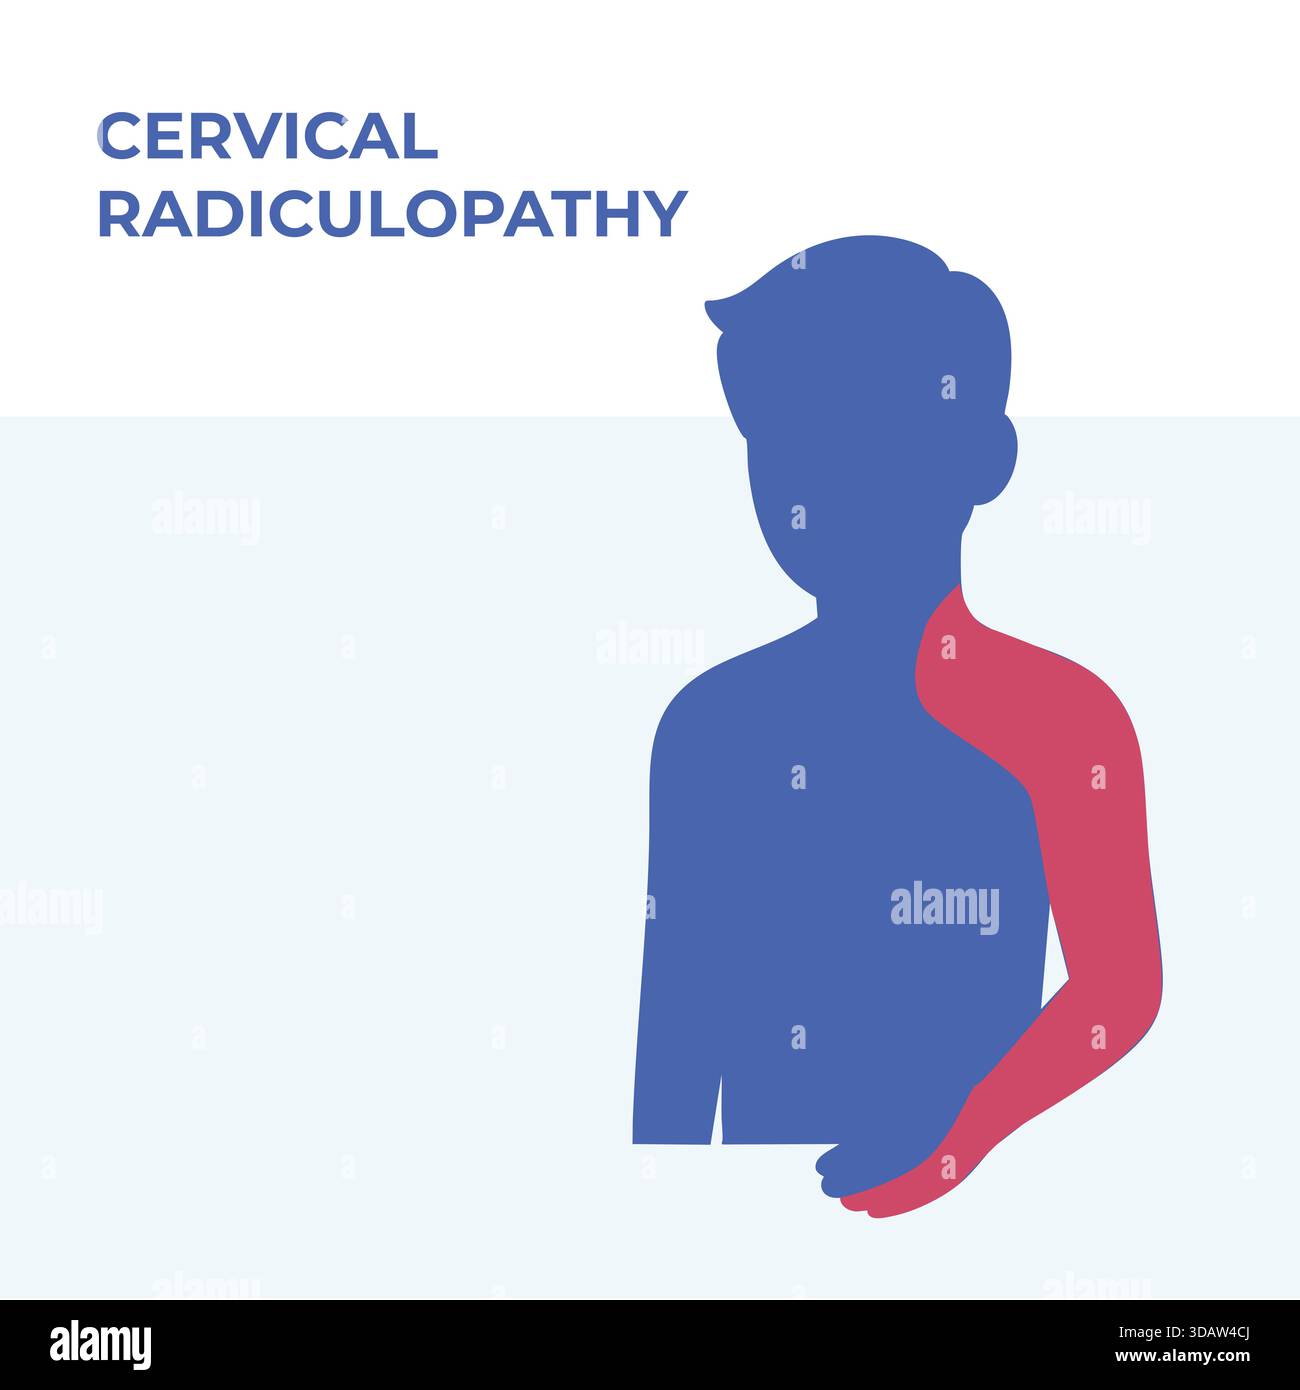

RF3DAW4CJ–Vektor-Illustration, die Schmerzverteilungsbereiche zeigt, die mit zervikaler Radikulopathie assoziiert sind, wobei Nacken-, Schulter- und Armregionen hervorgehoben werden. Vereinfacht

RF3DAW4CE–Vektormedizinische Illustration der zervikalen Radikulopathie mit Bandscheibenvorfall und entsprechenden Schmerzbereichen in Hals, Schulter und Oberschenkel.